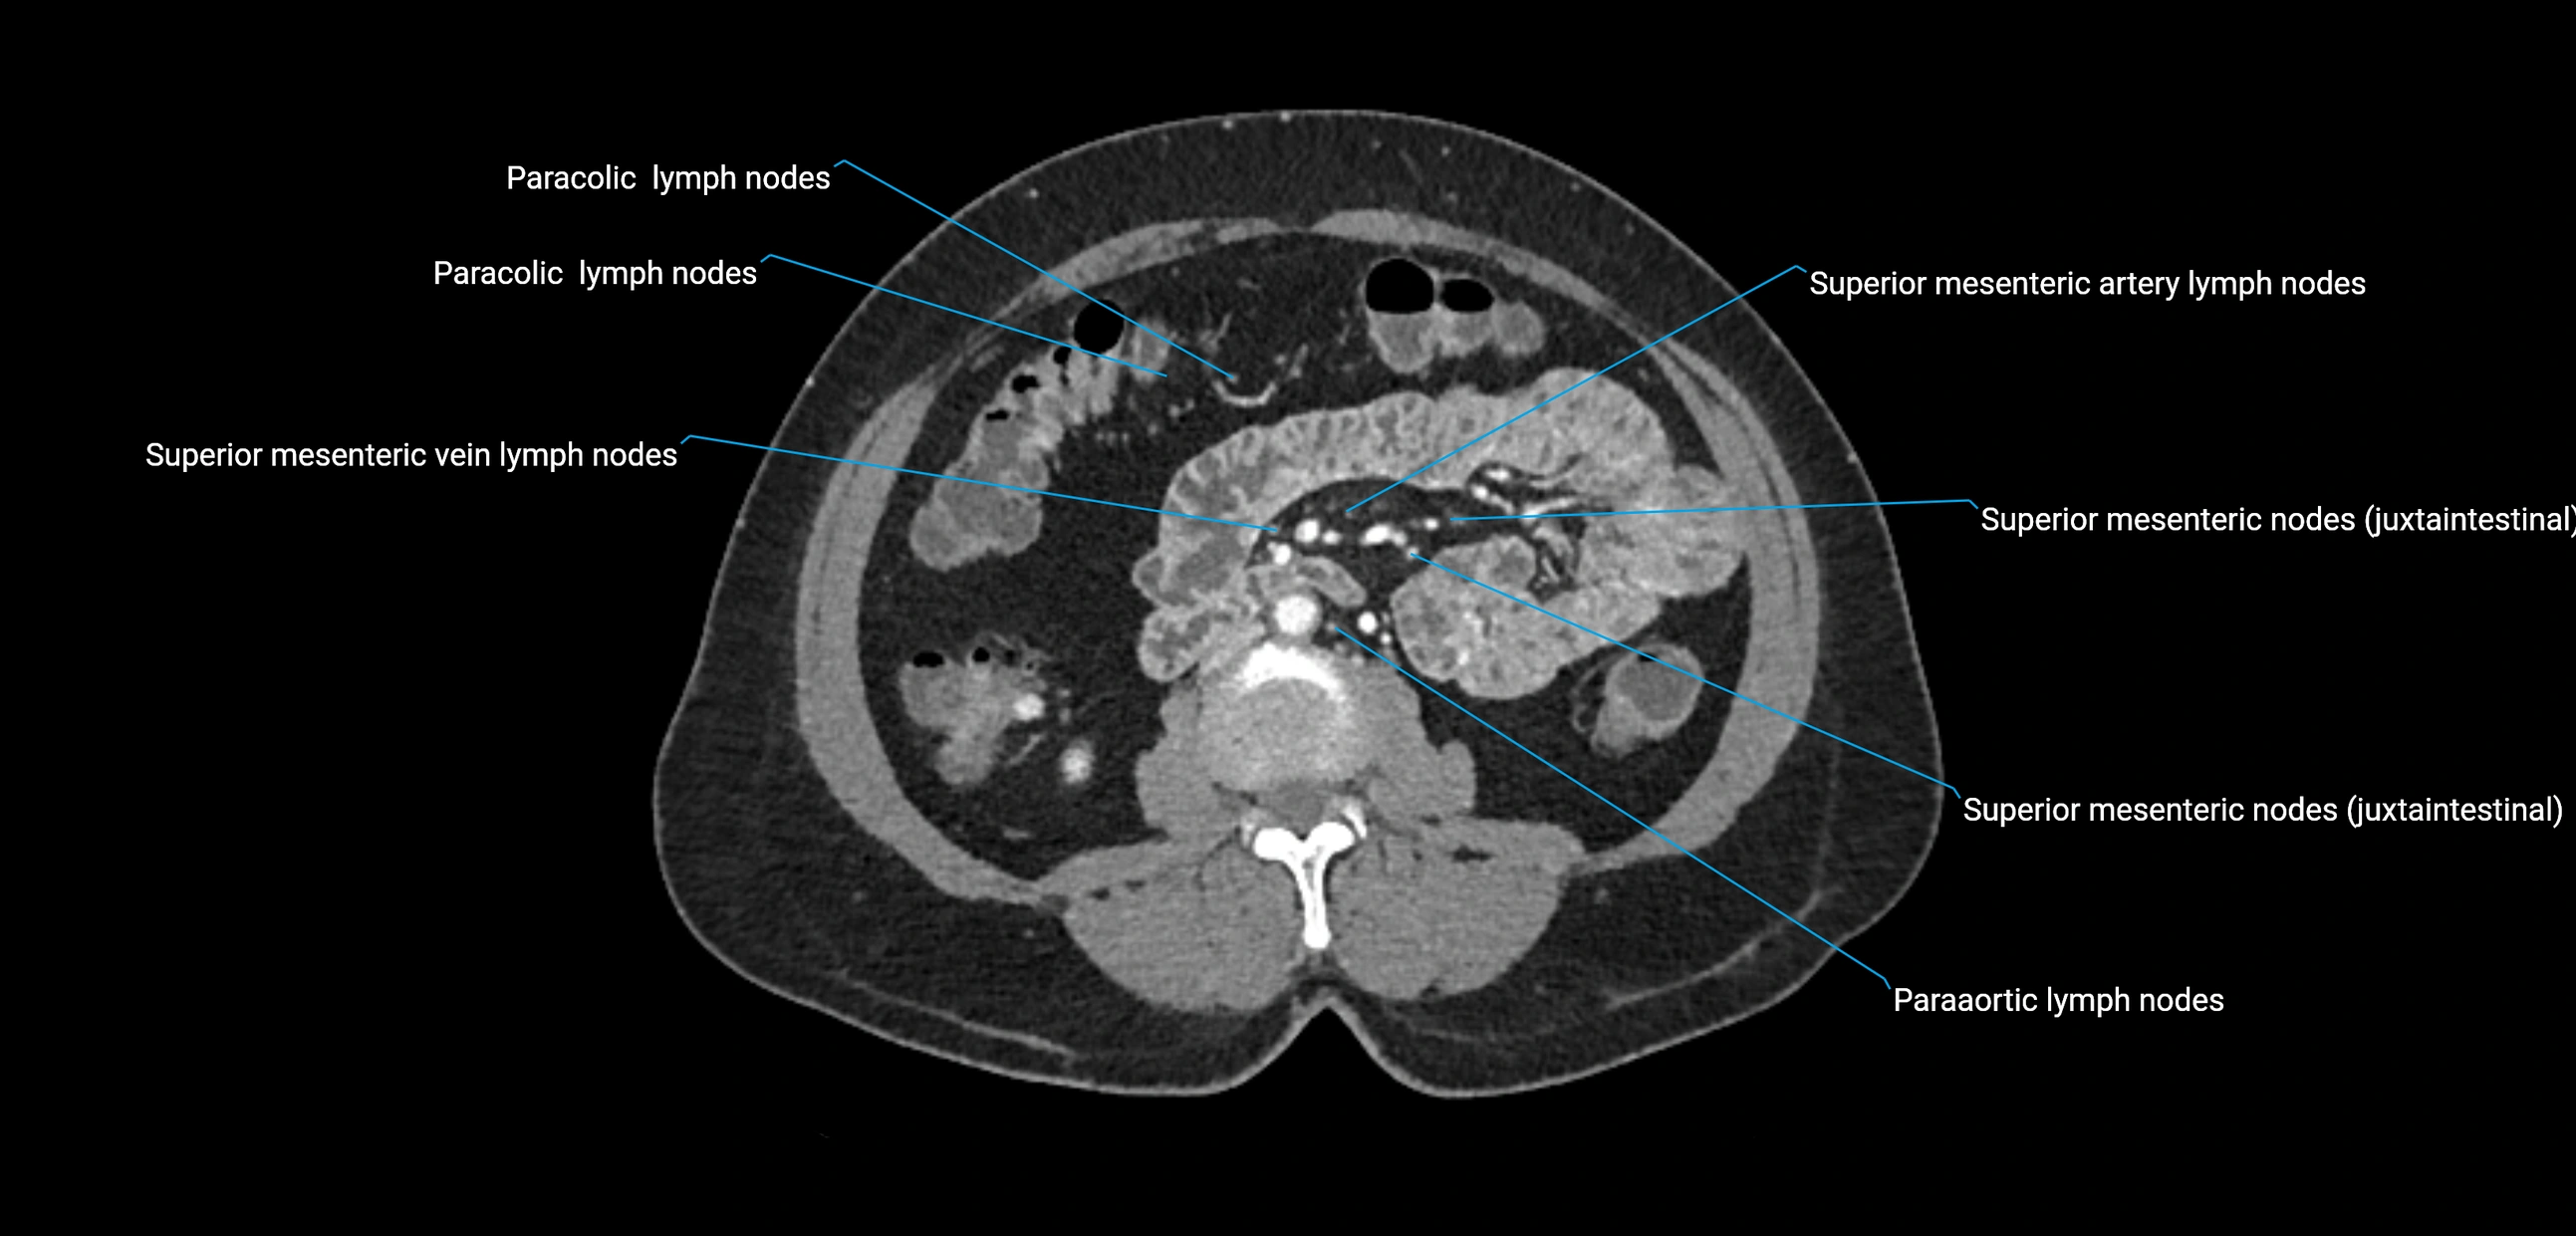

CT Appearance

CT Pre-Contrast:

• Nodes appear as soft-tissue density nodules adjacent to the aorta and IVC

• Calcification may be seen in chronic infections (e.g., tuberculosis)

CT Post-Contrast:

• Normal nodes enhance homogeneously

• Malignant nodes may show heterogeneous enhancement, central necrosis, or conglomerate formation

• Size >1 cm short axis is suspicious, though morphology and distribution are equally important